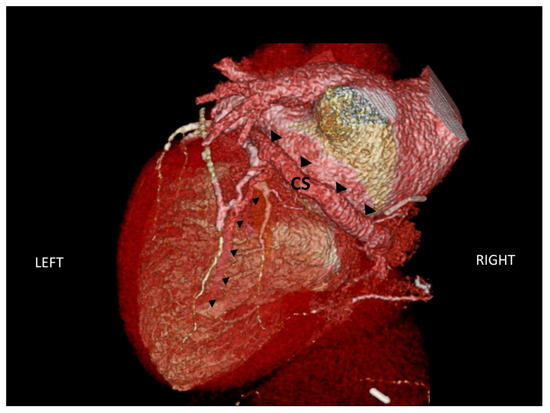

2.3. Assessment of Cardiac Venous Anatomy

- Van de Veire, N.R.; Schuijf, J.D.; De Sutter, J.; Devos, D.; Bleeker, G.B.; de Roos, A.; van der Wall, E.E.; Schalij, M.J.; Bax, J.J. Non-invasive visualization of the cardiac venous system in coronary artery disease patients using 64-slice computed tomography. J. Am. Coll. Cardiol. 2006, 48, 1832–1838. [Google Scholar] [CrossRef] [PubMed]

- Girsky, M.J.; Shinbane, J.S.; Ahmadi, N.; Mao, S.; Flores, F.; Budoff, M.J. Prospective randomized trial of venous cardiac computed tomographic angiography for facilitation of cardiac resynchronization therapy. Pacing Clin. Electrophysiol. 2010, 33, 1182–1187. [Google Scholar] [CrossRef] [PubMed]